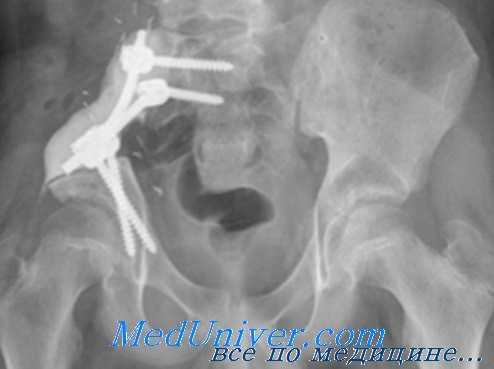

Прежде всего, необходимо диагностировать кровотечение и определить его локализацию. У пострадавших с продолжающимся тазовым кровотечением, реанимационные и лечебные мероприятия проводятся одновременно. Приоритетным направлением в лечении остается остеосинтез с использованием разной техники проведения операции. Если кровотечение не остановлено, окончательный гемостаз может быть выполнен путем ангиографической эндоваскулярной эмболизации, и/или путем применения хирургической техники. При обследовании стабилизированных больных можно использовать методы дополнительной визуализации.

Во многих случаях при лапаротомии диагностируется как тазовое, так и внутрибрюшное кровотечение. Если в брюшной полости обнаружена гематома, следует быстро восстановить целостность передней брюшной стенки, и транспортировать больного в кабинет ангиографии. Немедленный хирургический контроль распространенной гематомы является ошибочной тактикой. Но при отсутствии возможности быстрого проведения ангиографии, выполнение открытой операции станет неизбежным.

После остановки кровотечения из крупных сосудов, выполняется стандартная ангиография. Ангиографию можно выполнить непосредственно во время операции для обнаружения и проведения эмболизации других потенциальных источников кровопотери. Во время ангиографии можно провести временное тампонирование таза для уменьшения капиллярного кровотечения.